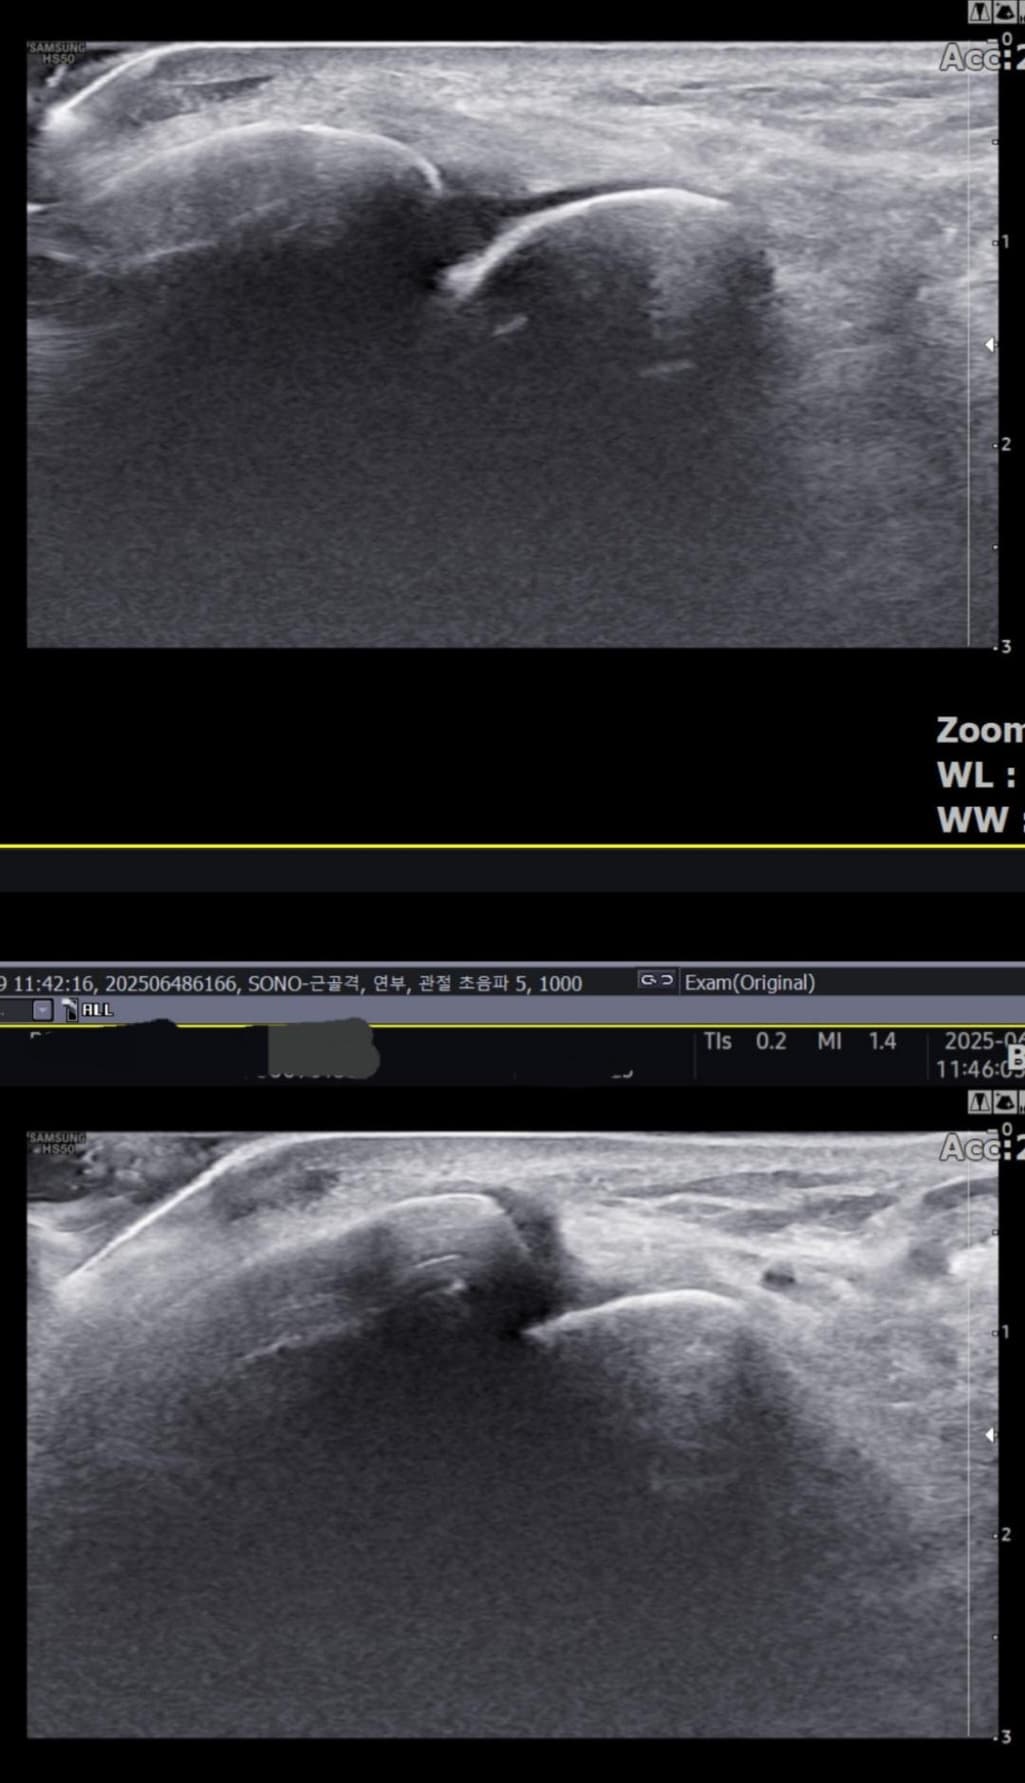

그런데 다친 지 2주 뒤부터 발목이 쑤시듯 아파 병원에서 초음파 검사를 했고, 전거비인대(ATFL) 2도 염좌 진단을 받았습니다. 이후 약 6주 동안 주 1회씩 충격파, 물리치료, 도수치료 등을 받았습니다. (고정치료는 시기가 늦었다며 진행하지 않았습니다.)

그리고, 처음 초음파 사진(6월 촬영)과 비교하여

초음파와 비교하면 mri 상으로 인대 연속성이 확인되므로 심각한 악화나 재파열은 아닌 것으로 판단됩니다